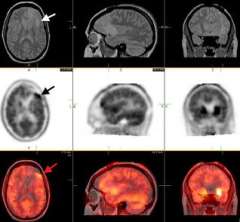

MRS: The upper right MRI shows an abnormal area in the right parietal lobe. A square "voxel" (marked by the arrow) is the area of interest within the tumor. The middle left MRS image shows the amount of choline (CHO) contained in each part of the brain. Areas of high CHO (arrow) suggest closer crowding of cells (such as a tumor). The lower left MRS shows that NAA (a chemical found in neurons, or brain cells) is low in the area of the tumor. Because tumor cells displace neurons, low NAA may also suggest tumor. In this case, a biopsy confirmed a low-grade astrocytoma.

PET: The upper panel images are MRI scans showing a small low-grade astrocytoma in the left frontal lobe (white arrow). The middle panel shows a FDOPA-PET with high uptake (black arrow) in an area immediately in front of the abnormality seen on MRI. The lower panel shows the fused (overlapping) MRI and PET images. At surgery, the area identified by PET revealed the diagnostic tissue.